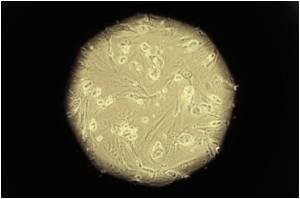

A synthetic material called Mebiol Gel was used as a scaffold to grow corneal stem cells from a rabbit. The gel actually aided in the multiplication of cells and prevents rejection of the new cells. The stem cells are then harvested and placed in a refrigerator after which they are injected into the eyes of the rabbits when needed.